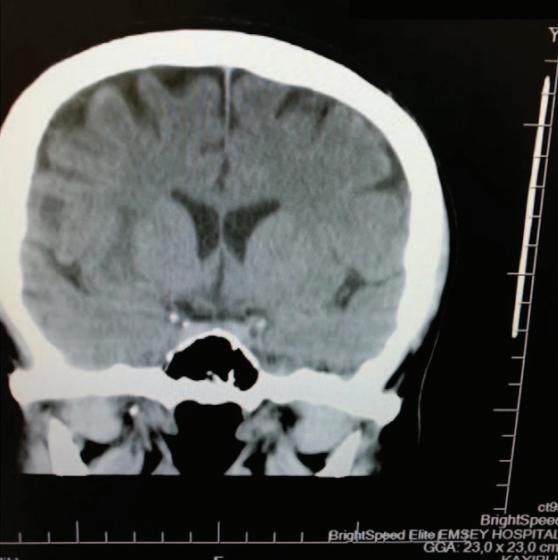

行影像学检查( 图1 )显示丘脑出血,诊断为脑卒中。

图1 头部计算机断层扫描:脊髓联合硬膜外麻醉后的右侧急性丘脑血肿。